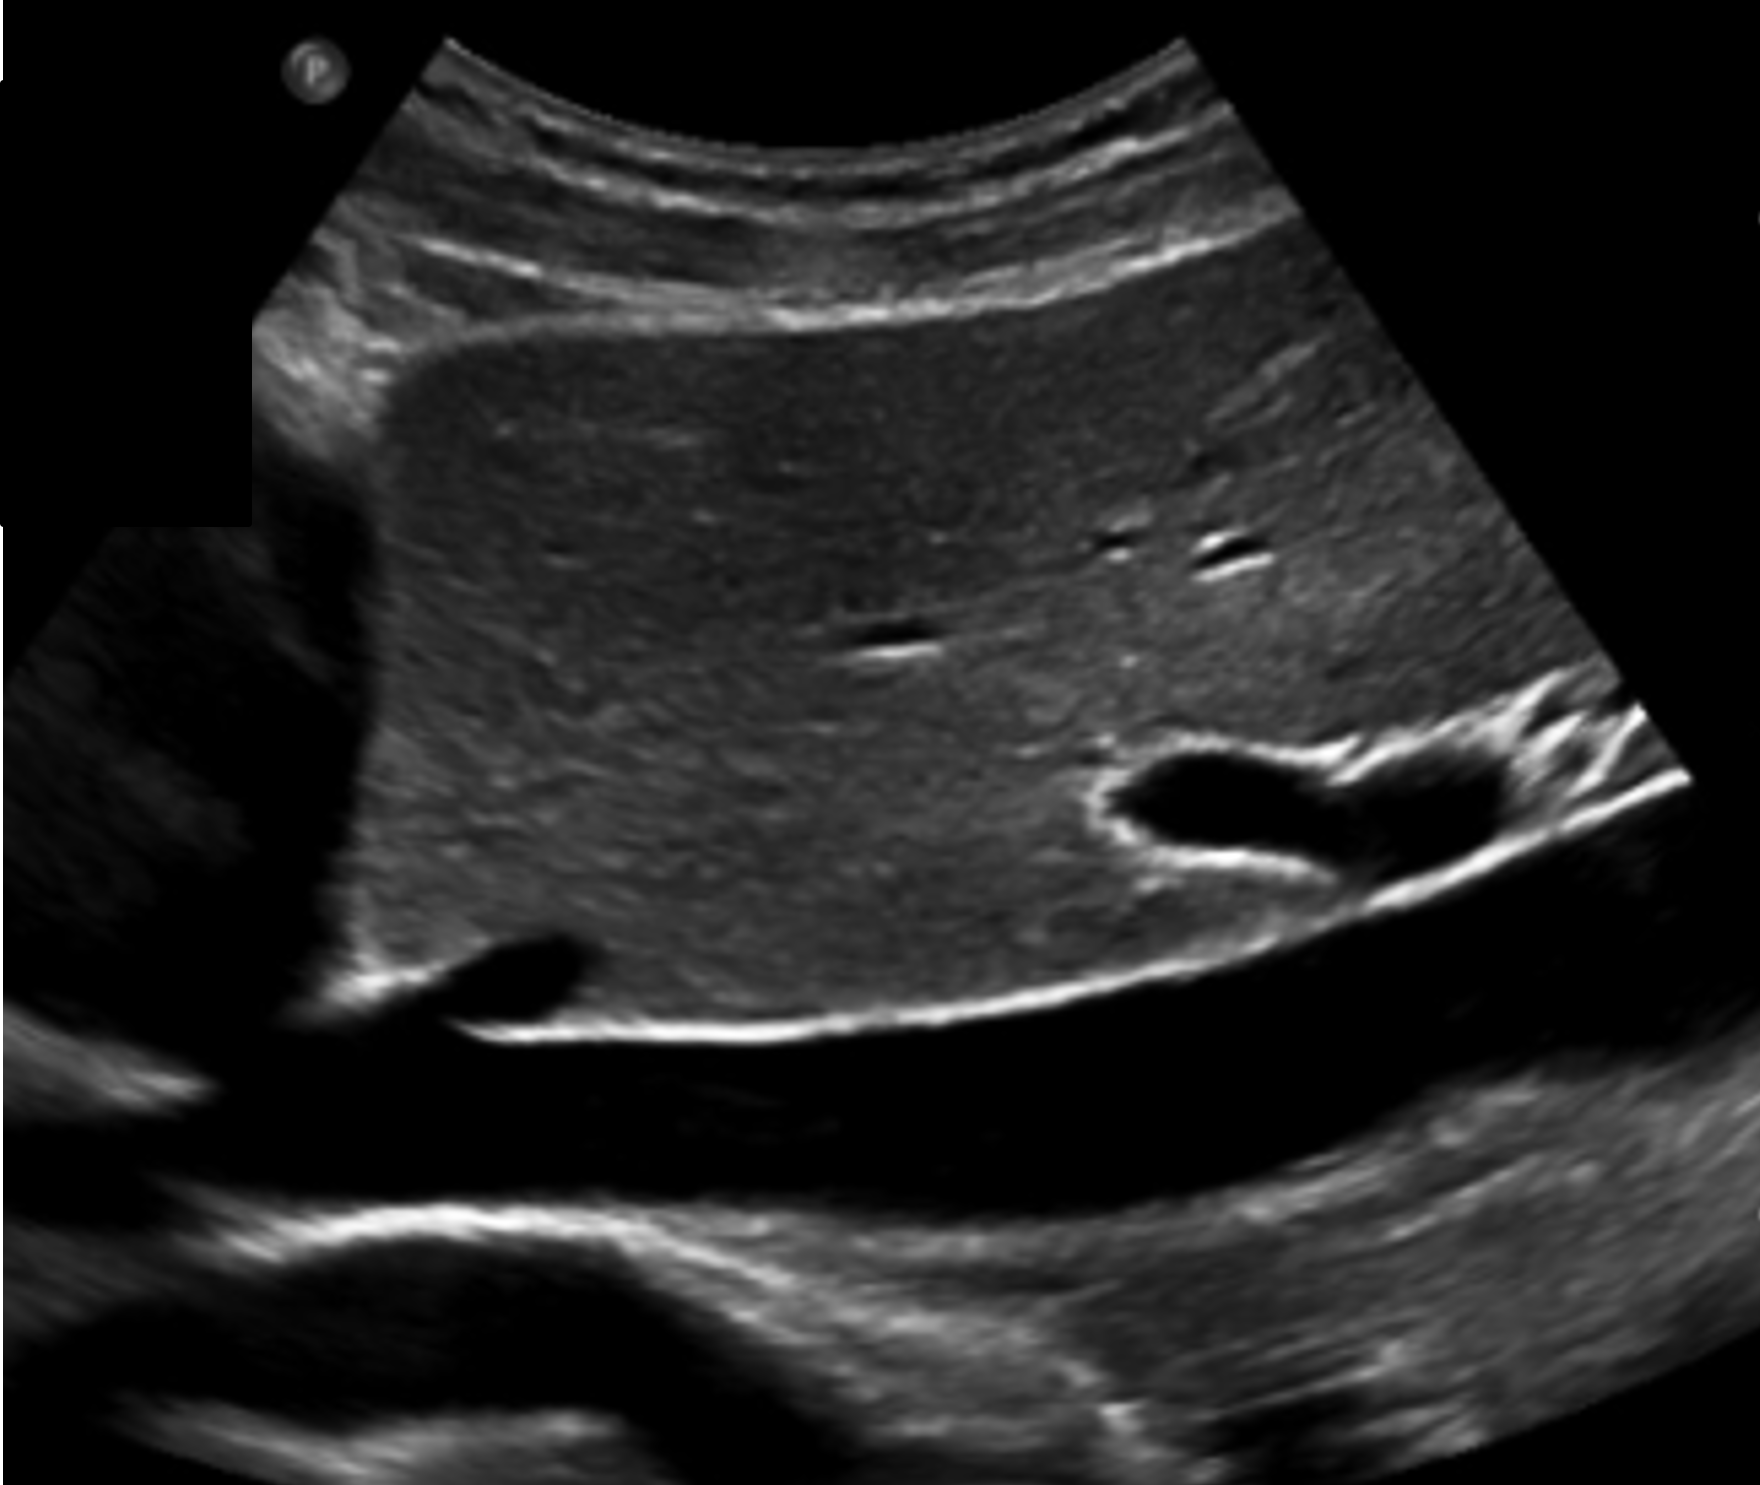

<p>What is this structure?</p>

What is this structure?

IVC

<p>What is this structure ?</p>

What is this structure ?

Abnormal Aorta

Aorta with the SMA coming off the top